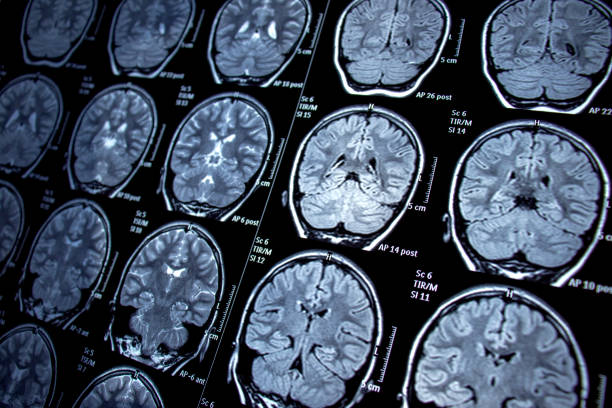

A renowned private hospital group on Friday unveiled a noninvasive treatment for brain tumours, that will ensure shorter stay in hospital and faster recovery. The Apollo Hospitals Group launched the ZAP-X Gyroscopic Radiosurgery platform.

He said the procedure time and outcomes depend on the size and types of tumours, and added that the platform offers real-time image guidance, shorter treatment duration and enhanced patient safety.

In brain tumours, there is a cancerous or non-cancerous mass or growth of abnormal cells in the brain.